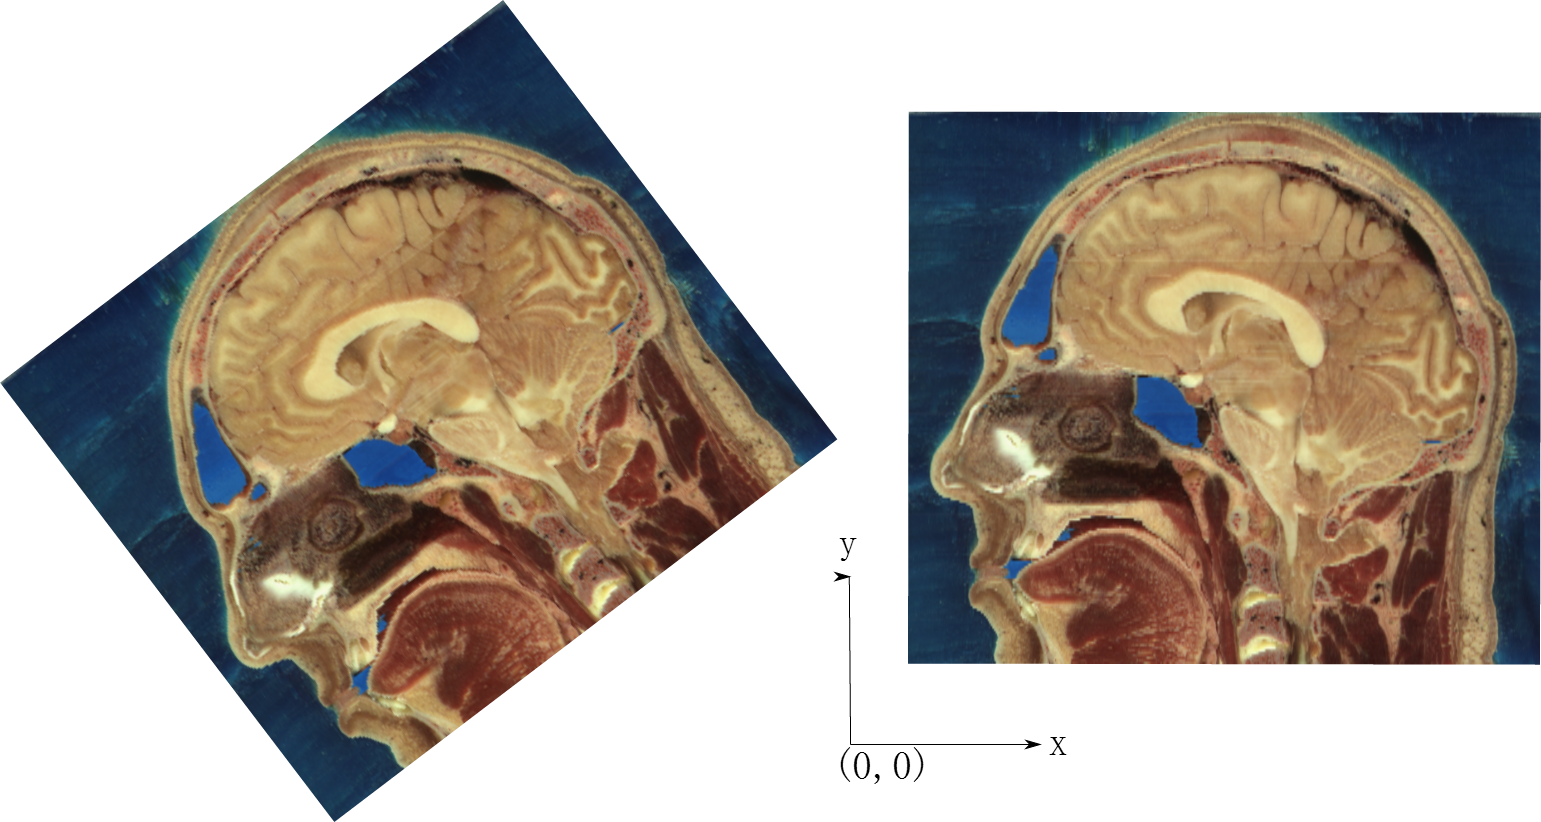

再看

两幅图内容一样,但是方向和坐标原点都不同,在SimpleITK中是不同的图像